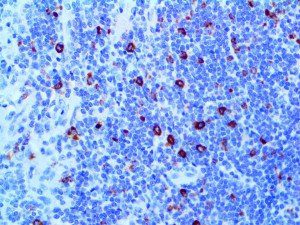

It is the ICU physician who is most likely to witness one of the deadliest manifestations of the abnormal immunological response, the cytokine storm syndrome (CSS). This response is also referred to by some as the cytokine release syndrome (CRS). CSS is characterized by continuous activation and expansion of macrophage and lymphocyte populations, which secrete large amounts of cytokines, causing the cytokine storm. This massive cytokine release is akin to hemophagocytic lymphohistiocytosis (HLH) disease, a syndrome characterized by initial unchecked and persistent activation of cytotoxic T lymphocytes and NK cells.

Clinical and laboratory manifestations of HLH include fever, enlarged liver and/or spleen, neurologic dysfunction, coagulopathy, liver dysfunction, cytopenias (i.e., low levels of erythrocytes, leukocytes, and/or platelets), hypertriglyceridemia, hyperferritinemia, hemophagocytosis, and eventually diminished NK cell activity as the immune system becomes progressively paralyzed. HLH can be familial (primary HLH) or secondary to another disease process (sHLH), such as rheumatic disease, in which it is referred to as macrophage activation syndrome (MAS, characterized by elevated ferritin).